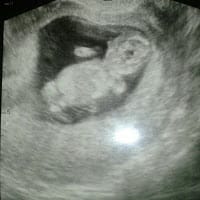

Siento la boca del estomago inflamada, siento mucho ardor y cada vez es más fuerte el ardor que ni un antiácido me alivia, me han recetado ranitidina, pero aún siguo con los ardores en la boca del estomago. Hiy fuu a una consulta pero ni quede muy...